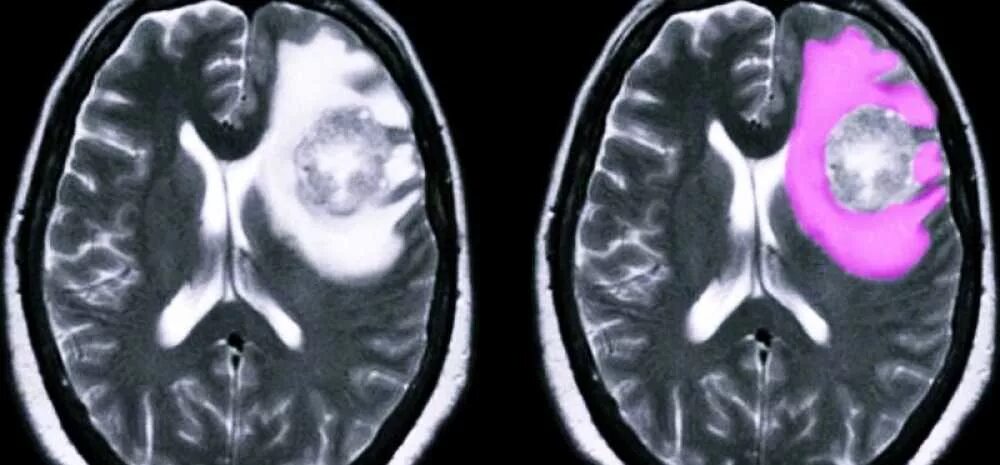

Отек головного мозга мрт